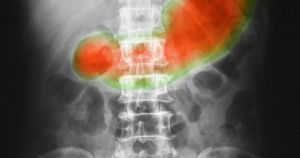

1. Co jest zaznaczone na grafice?

Obraz